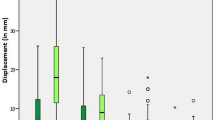

Descriptive statistics were used to compare the demographic and clinical characteristics in the two cohorts (Table 1). Student’s t-test and chi-square tests were used to test for differences in the distribution of clinical characteristics between the two cohorts. Student’s t-test tested for differences in radiation dose between the two cohorts. Bland–Altman methods were used to evaluate the accuracy of the LCEA measurements according to the two radiographic modalities (Fig. 5). Accuracy was calculated as the difference between the intraoperative and six-week postoperative radiographs. The six-week postoperative X-ray measurement was used to represent the gold-standard radiographic measurement. Performance of both radiographic methods relative to this gold-standard were evaluated based on bias, or mean difference, and corresponding 95% limits of agreement. In this analysis, three degrees was considered clinically meaningful24.

Accuracy

The bias, or mean difference, between the intraoperative and 6-week postoperative LCEA measurements was 0.36° for the SFII cohort and 0.27° for the FPD cohort. The limits of agreement were [− 3.19 to 2.47] for the SFII cohort and [− 2.05–2.59] for the FPD cohort.

Use of a novel imaging modality necessitates that the visualization of pelvic anatomy, performance of osteotomies, and acetabular reorientation is possible with the same quality as the previous standard of care. The benefit of reduction in intraoperative radiation exposure during PAO must be accompanied by similar image quality, and the ability to achieve similar results as compared to the SFII. In this case, the bias, or difference between the intraoperative and postoperative radiographs, was low in both groups without a significant difference in LCEA. Importantly, neither machine consistently over- nor under-estimated the intraoperative LCEA as compared to its respective patient’s postoperative LCEA. Additionally, on direct visual estimation, both the SFII and FPD produced similar quality images as observed by viewing the two images side by side (Fig. 6). Overall, these results indicate no significant difference between the image quality produced by the FPD fluoroscope as compared to the SFII.